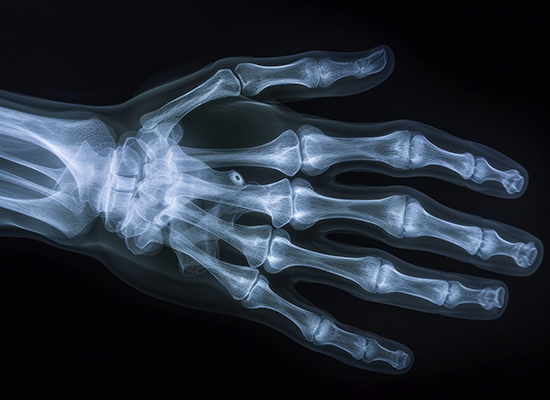

Röntgendiagnostik

Konventionelle Röntgenaufnahmen dienen vor allem der Beurteilung der Knochenstruktur sowie der Gelenke. Sie werden auch zur Basisdiagnostik von Herz- und Lungenerkrankungen eingesetzt.